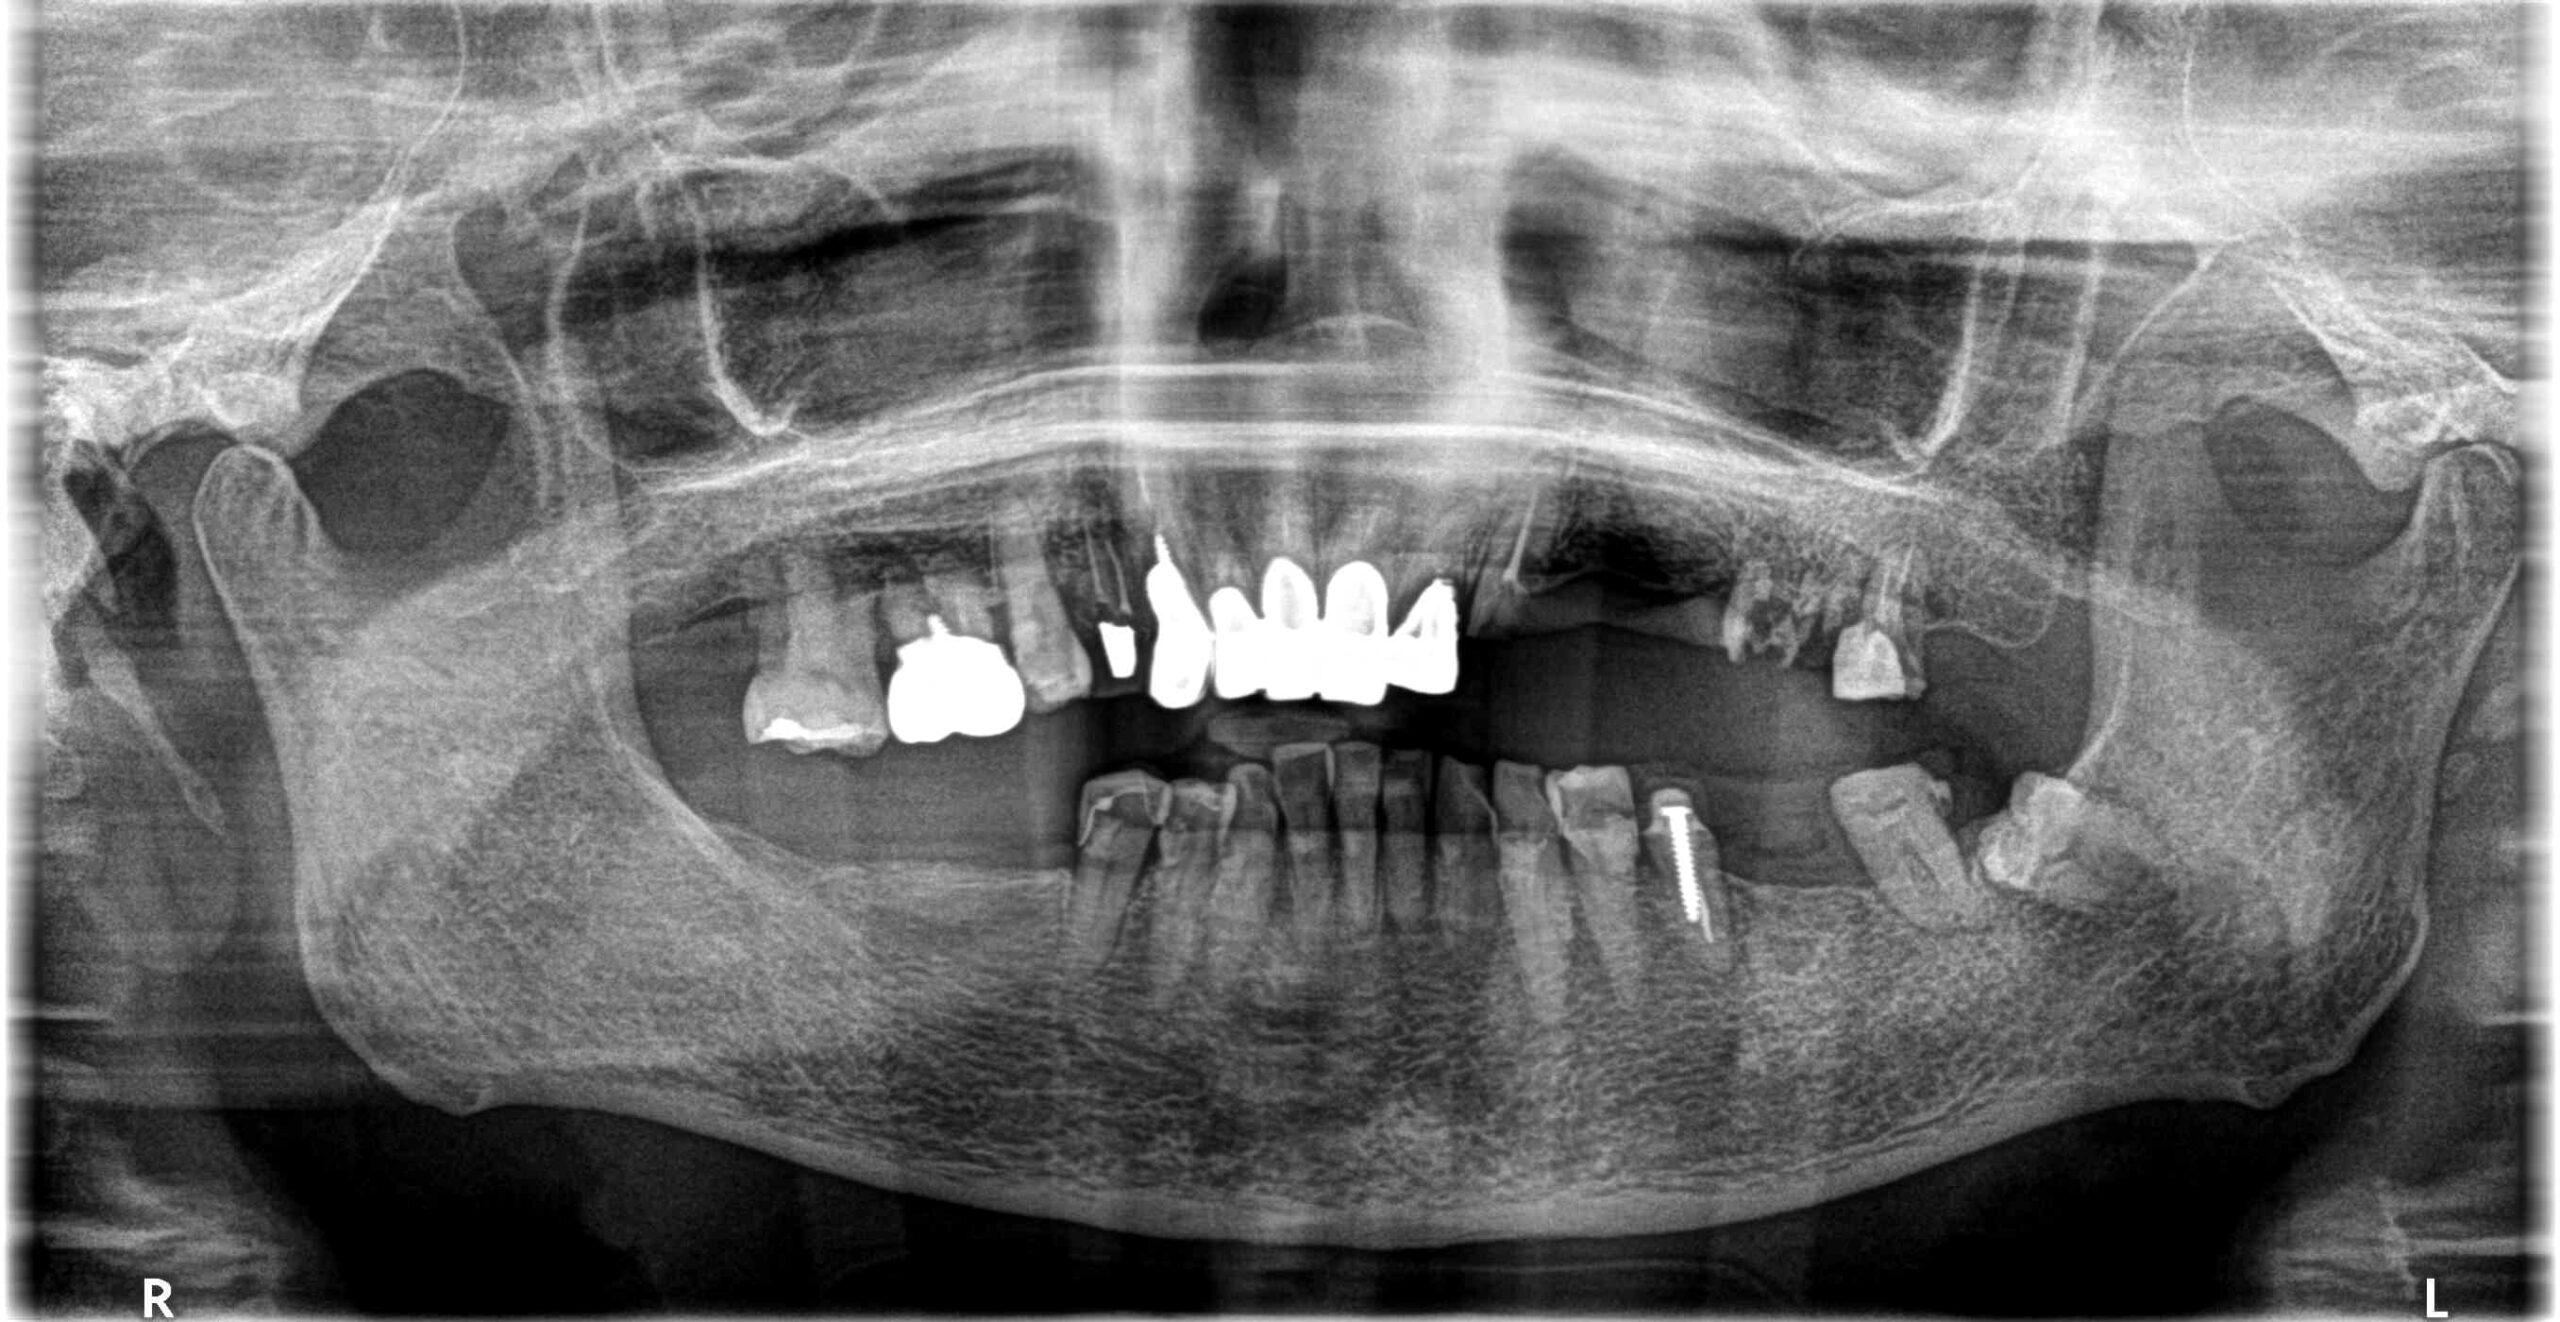

治療経過 高齢ではあったが、入れ歯はどうしてもいれたくないということでインプラントを選択。

上顎は長期的な予後が見込める歯が少なく多数のインプラントを必要としたが、一時的にも義歯を使うことなく、咬める場所を温存しながらインプラントへと移行できた。

初診時不安定だった咬み合わせもスムーズに行えるようになり、不安なく食事ができるお口の状態を獲得できた。